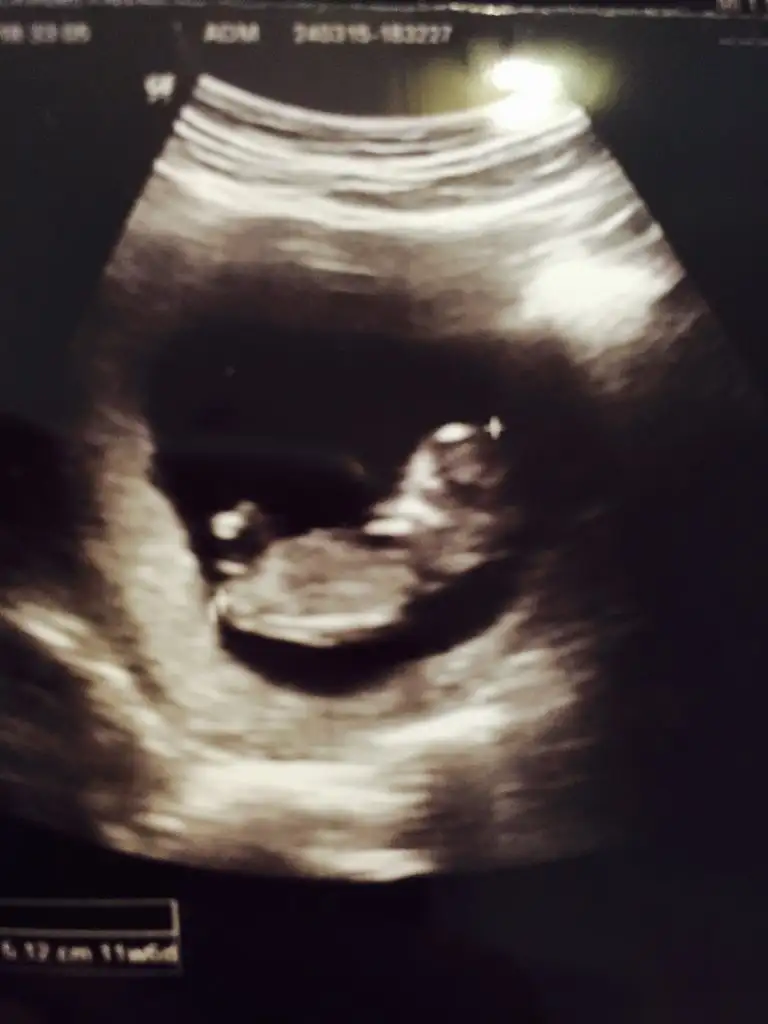

canım kıza benziyor, sağlıkla gelsin inşallahEki Görüntüle 1468834 Eki Görüntüle 1468838 Eki Görüntüle 1468832 Kizlar merhaba bende iyi tahmin edenlerden bir yorum alabilirmiyim acaba??

Allah gonlune gore versinYaaa insallah bana bi fotografta bariz kiz gibi geldi digerlerinde bi cikinti var doktora sordum bu cikintimi diye hayir o kordonu bosuna cikinti arama su an icin erken dedi ayy nasil sabredicem 1 ay daha bilmiyorum..yorum icin cok tesekkurler canim..bacak arasina falan girdi bakti ben hic cikinti goremedim ama tabi doktor varsa da gormustur

Canimm cok tesekkur ederim yorumun icin insallah saglikli bi kiz gelsincanım kıza benziyor, sağlıkla gelsin inşallah

Kiz agrim var de sancim var de git başka bir doktora...Bence başka doktora git çünkü doktorun bence anlamio her seferinde kordonu paha ne edioHayırlısı artık canım benim çoksağol hayır kız erkek farketmezde insan heves ediyo bişey görüyon almak istiyosun olmuyo artık bir aydaha bekle işin yoksa of of neyse ya Allahın gücüne gitmesin hakkımızda hayırlısi vardır onunda bir zamanı